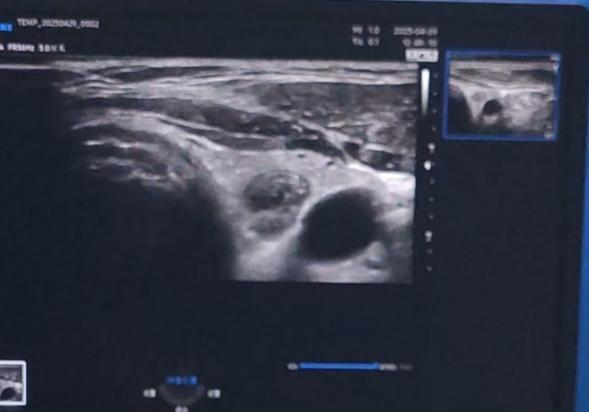

体检发现「甲状腺右侧叶囊性结节伴浓缩胶质回声」,这一消息让 40 岁的李女士寝食难安。今年 4 月底,她来到武汉大学人民医院(湖北省人民医院)内分泌科高凌主任处就诊。

高凌教授接诊详细了解患者病情资料后,凭借丰富的临床经验,立即诊断患者出现了「甲状腺结节」。由于患者有甲状腺癌家族史,因此有必要及早诊治。

手术当天,主导医师在超声设备的引导下,对病灶定位确定治疗点;然后使用微波针「以针代刀」,通过针尖大小的创口,利用微波的热效应和冷循环系统的协同作用,精准、有效地消融病变组织,同时降低对周围正常组织的不良影响。